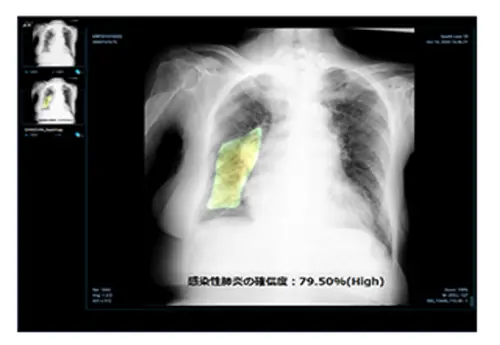

제이엘케이는 지난 9일 일본 PMDA가 동사의 폐질환 솔루션 JVIEWER-X에 대한 인증을 최종 허가했다고 16일 밝혔다. 엑스레이 (X-Ray) 영상을 기반으로 한 감염성 폐렴 검출 인공지능 솔루션에 대한 PMDA승인은 일본 최초이다. 신형 코로나 바이러스 폐렴을 포함한 감염성 폐렴의 영상 진단을 지원하는 이 솔루션은 초고령화 사회로 접어든 일본에서 지난 1년간 광범위한 수준의 임상 데이터에 대한 검증이 진행된 만큼 다른 선진 국가에서도 그 활용성이 확대될 것으로 예상된다. 일본에서 폐렴은 전체 사망원인의 3위를 차지할 만큼 심각한 질환으로, 일본 정부의 폐렴 치료에 대한 관심과 투자는 각별하다. 섬나라 특성상 대면 진료가 어려운 경우가 많고 코로나19에 대한 국가 차원의 빠른 대응이 부족했던 점도 제이엘케이의 폐질환 솔루션이 긴급하게 승인된 배경으로 보인다.

이 솔루션은 시중 클리닉이나 병원에서도 X-Ray 촬영을 통해 방사선 진단 전문의 수준의 정밀도로 영상을 판독하여 감염성 폐렴 유무를 검출할 수 있다. 특히, 가장 보편적인 엑스레이 영상을 기반으로 코로나에 의한 폐렴 조기 검출 및 스크리닝은 JVIEWER-X가 처음인데다가, 폐질환의 중증도 분류나 악화 여부의 추적 관찰 등 전주기적인 활용 가능성도 입증했다.